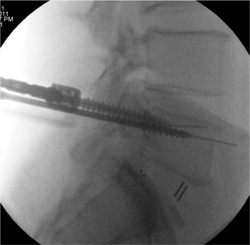

K-wire Complication

A serious potential complication can arise from insertion of

the K-wire beyond the anterior aspect of the vertebral body

( Figure 7 ). This can either occur from aggressive advancement

of the K-wire down the barrel of the Jamshidi, osteoporotic

bone with poor tactile feedback when inserting the

K-wire, or with the K-wire inadvertently moving distally

with advancement of the pedicle tap.

There are no reports in the literature that discuss complication

rates from anterior placement of a K-wire at the

time of percutaneous pedicle screw placement. All cases of

anterior placement of K-wires were prospectively recorded,

and any subsequent complications noted such as blood loss

or ileus.

There were 4 anterior K-wire perforations (0.9% of all

screws) during the course of the study period. One case was

because of advancement of the K-wire at the time of tapping

the pedicle, 2 cases were because of osteoporotic bone with

poor tactile feedback for the surgeon and 1 case of forceful

advancement of the K-wire with anterior puncture of the

vertebral body ( Figure 7 ). From the 4 cases identifi ed with

K-wire perforation, 1 patient had a small volume retroperitoneal

bleed and ileus treated conservatively. The other 3

patients had an uneventful recovery postoperatively.

Prospective analysis of K-wire complications revealed 4

anterior breaches ( Figure 7 ). There is minimal data in the literature

on the potentially devastating complication of vascular and abdominal injury with this technique. The authors documented

all cases and any subsequent complications. There

was a single complication of retroperitoneal hemorrhage and

ileus that improved with conservative measures. The senior

author places all patients with anterior K-wire breach on

broad spectrum antibiotics assuming there has been an intestinal

puncture. It is paramount that the senior surgeon remind

the assistant during the procedure that meticulous care be

taken with stabilizing the K-wire when multiple instruments

and the pedicle screw are placed over the guide K-wire.

Figure 7. K-Wire complication. Care must be taken with K-wire insertion to ensure that the K-wire is not aggressively advanced into the vertebral body with puncture through the anterior aspect of the vertebra.